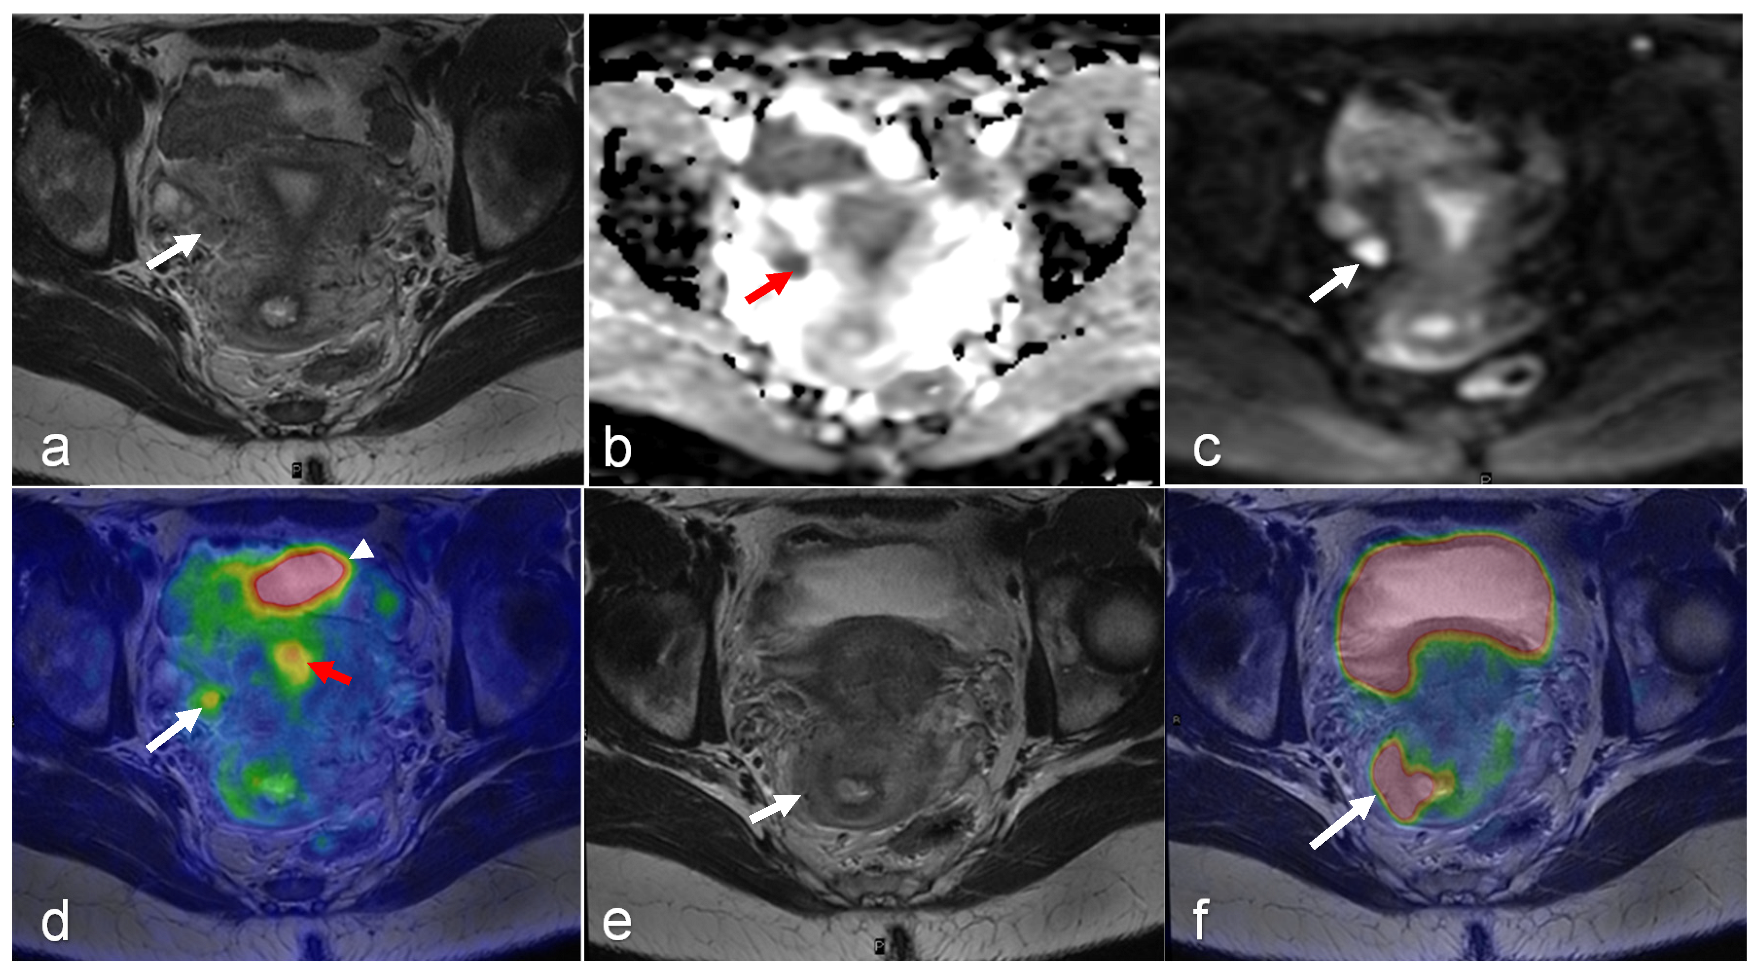

- Shih, I.L.; Yen, R.F.; Chen, C.A.; Cheng, W.F.; Chen, B.B.; Chang, Y.H.; Cheng, M.F.; Shih, T.T. PET/MRI in Cervical Cancer: Associations Between Imaging Biomarkers and Tumor Stage, Disease Progression, and Overall Survival. J. Magn. Reson. Imaging 2021, 53, 305–318. [Google Scholar] [CrossRef] [PubMed]

- Brandmaier, P.; Purz, S.; Bremicker, K.; Hockel, M.; Barthel, H.; Kluge, R.; Kahn, T.; Sabri, O.; Stumpp, P. Simultaneous [18F]FDG-PET/MRI: Correlation of Apparent Diffusion Coefficient (ADC) and Standardized Uptake Value (SUV) in Primary and Recurrent Cervical Cancer. PLoS ONE 2015, 10, e0141684. [Google Scholar] [CrossRef] [PubMed]

- Grueneisen, J.; Beiderwellen, K.; Heusch, P.; Buderath, P.; Aktas, B.; Gratz, M.; Forsting, M.; Lauenstein, T.; Ruhlmann, V.; Umutlu, L. Correlation of standardized uptake value and apparent diffusion coefficient in integrated whole-body PET/MRI of primary and recurrent cervical cancer. PLoS ONE 2014, 9, e96751. [Google Scholar] [CrossRef] [PubMed]